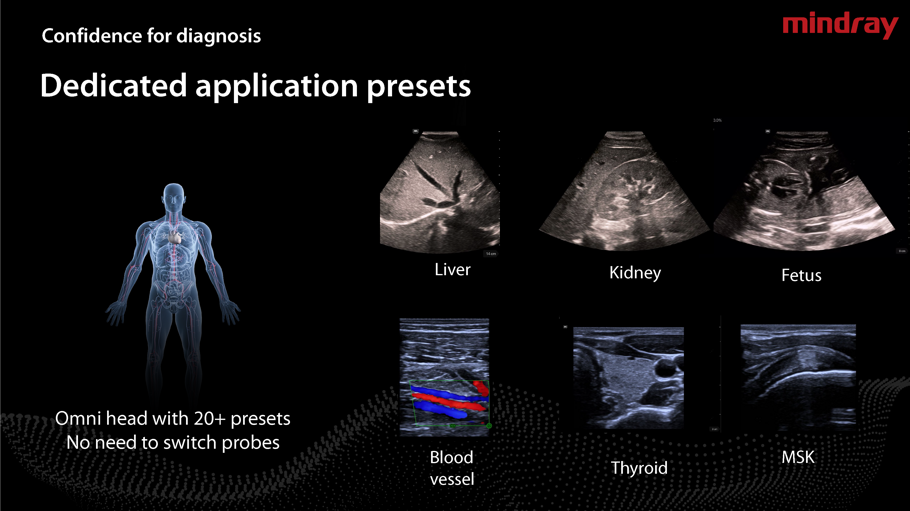

- Oltre 10 Preset di base e possibilità di personalizzarlo.

- Sistema Preconfigurato come Device in telemedicina.

Caratteristiche Generali Sistemi Wireless Serie LU700 , LK128:

- Alta risoluzione e tempo di utilizzo a lunga durata,fino a 4 ore di autonomia.

- Applicazione intuitiva,misure Doppler in tempo reale.

- Sonde a frequenza variabile,Color Doppler,Pulsed Wave,Power Doppler.

- Armonica di tessuto,Spacial Compound ,Connessione WiFi e USB ,velocità wireless elevato.